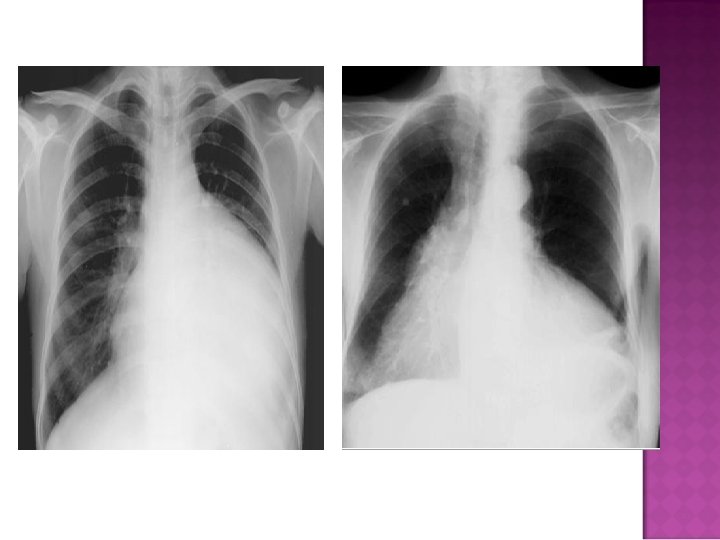

� Sudden inc in size of cardiac silhouette w/o specific chamber enlargement � Effacement of the normal cardiac borders � Development of a “flask” or “H 2 O-bottle” shaped heart

�May have (+) fat pad sign �Separation of mediastinal / retrosternal fat and epicardial fat by > 2 mm

Normal in patients with acute pericarditis unless pericardial effusion is present Enlarged cardiac silhouette Requires 200 cc of fluid